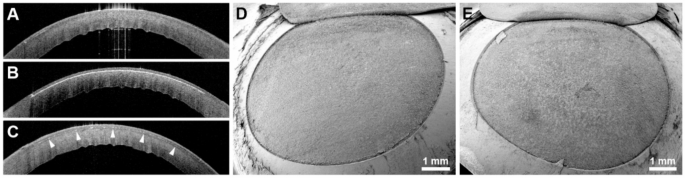

Of the 6 attempts of UV femtosecond laser treatment in 6 different human eyes with the corneal epithelium still in place, only one had been successful. Only the eye with a postmortem time of 6 h showed clear signs of UV femtosecond laser cuts despite the corneal epithelium being still intact. Here, refractive lenticule extraction and cap lift were possible. The cutting lines were easily discernible in the corresponding AS-OCT image (Fig. 2C, upper part) and the lenticule bed surface was accessible after lifting and reflection of the lenticule cap. The interface exhibited pronounced surface roughness and conspicuous irregularities (Fig. 2C, lower part). In all other corneas that still possessed their epithelium and that had been subjected to considerably longer postmortem times (see Table 1), the creation of stromal cutting planes was impossible with the UV femtosecond laser. Consequently, no cutting lines were discernible in AS-OCT (Figs. 2A, 3A) and the corneal stroma remained inaccessible by SEM (Fig. 2A) in these cases. After abrasion of the corneal epithelium, stromal lenticule and flap creation worked well with the UV laser, irrespective of the postmortem time. Thus, the corresponding AS-OCT images displayed clear cutting lines (Figs. 2B,D and 3B) and SEM analysis yielded smooth and regular lenticule beds (Figs. 2B,D and 3D). The infrared femtosecond laser was able to create a morphologically normal stromal flap through an intact corneal epithelium after 33 h postmortem (Fig. 3C,E).

Human corneas after flap creation at 33h p.m. with ultraviolet and infrared femtosecond lasers. (A–C) AS-OCT images of corneal cross-sections. (D, E) SEM images of lamellar beds after successful flap lift (oblique views). (A) Unsuccessful attempt by UV laser without prior abrasion of the corneal epithelium. No cutting line discernible. (B) Successful attempt by the UV laser in the same specimen after abrasion of the corneal epithelium. White cutting line along the interface discernible in the anterior stroma. (C) Successful attempt by an infrared femtosecond laser in the contralateral eye without abrasion of the corneal epithelium. The white cutting line appears thin but discernible (arrowheads). (D) Stromal bed of a flap created by the UV laser after abrasion of the corneal epithelium. The interface appears smooth and regular. (E) Stromal bed of a flap created by an infrared laser without prior abrasion of the corneal epithelium. The interface appears smooth and regular.